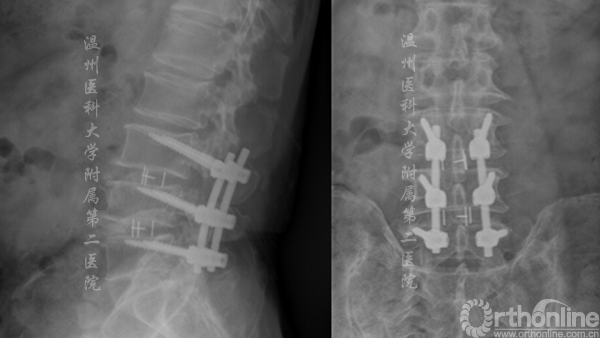

案例1

腰4/5腰椎管狭窄,行单节段CBT螺钉固定

术前MRI提示:腰4/5管狭窄(左) 术后X线提示:固定良好(右)